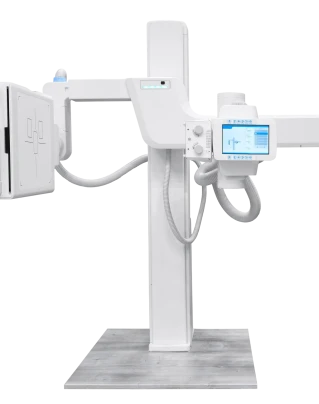

Метод безопасен, доступен и занимает всего несколько минут. В CHH в Краснознаменске рентген позвоночника выполняют на современном цифровом оборудовании с минимальной лучевой нагрузкой — результаты доступны сразу после процедуры.

Своевременная рентгенография отдела позвоночника позволяет выявить даже минимальные отклонения и предупредить осложнения. В клинике CHH в Краснознаменске диагностику проводят на современном цифровом оборудовании — процедура занимает несколько минут, результаты доступны сразу после обследования.